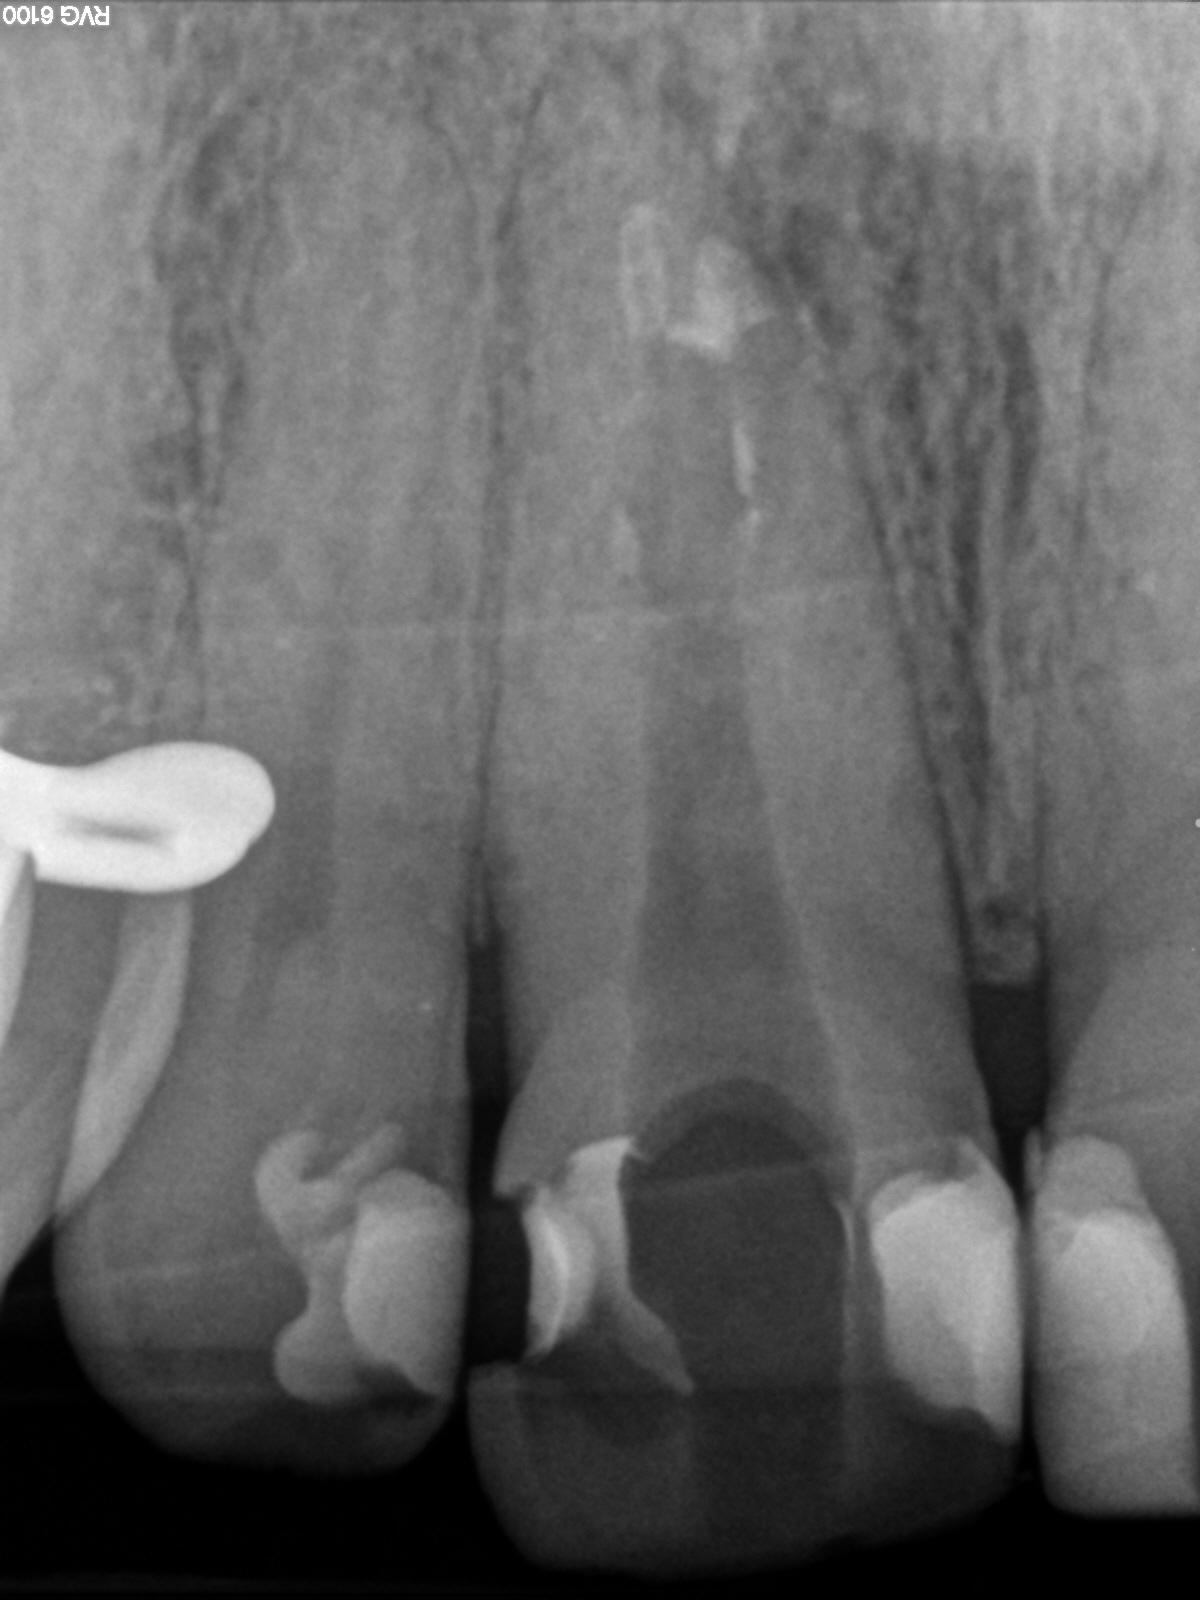

R7

Manchmal… (2)

MTA Plug und Reste der alten WF